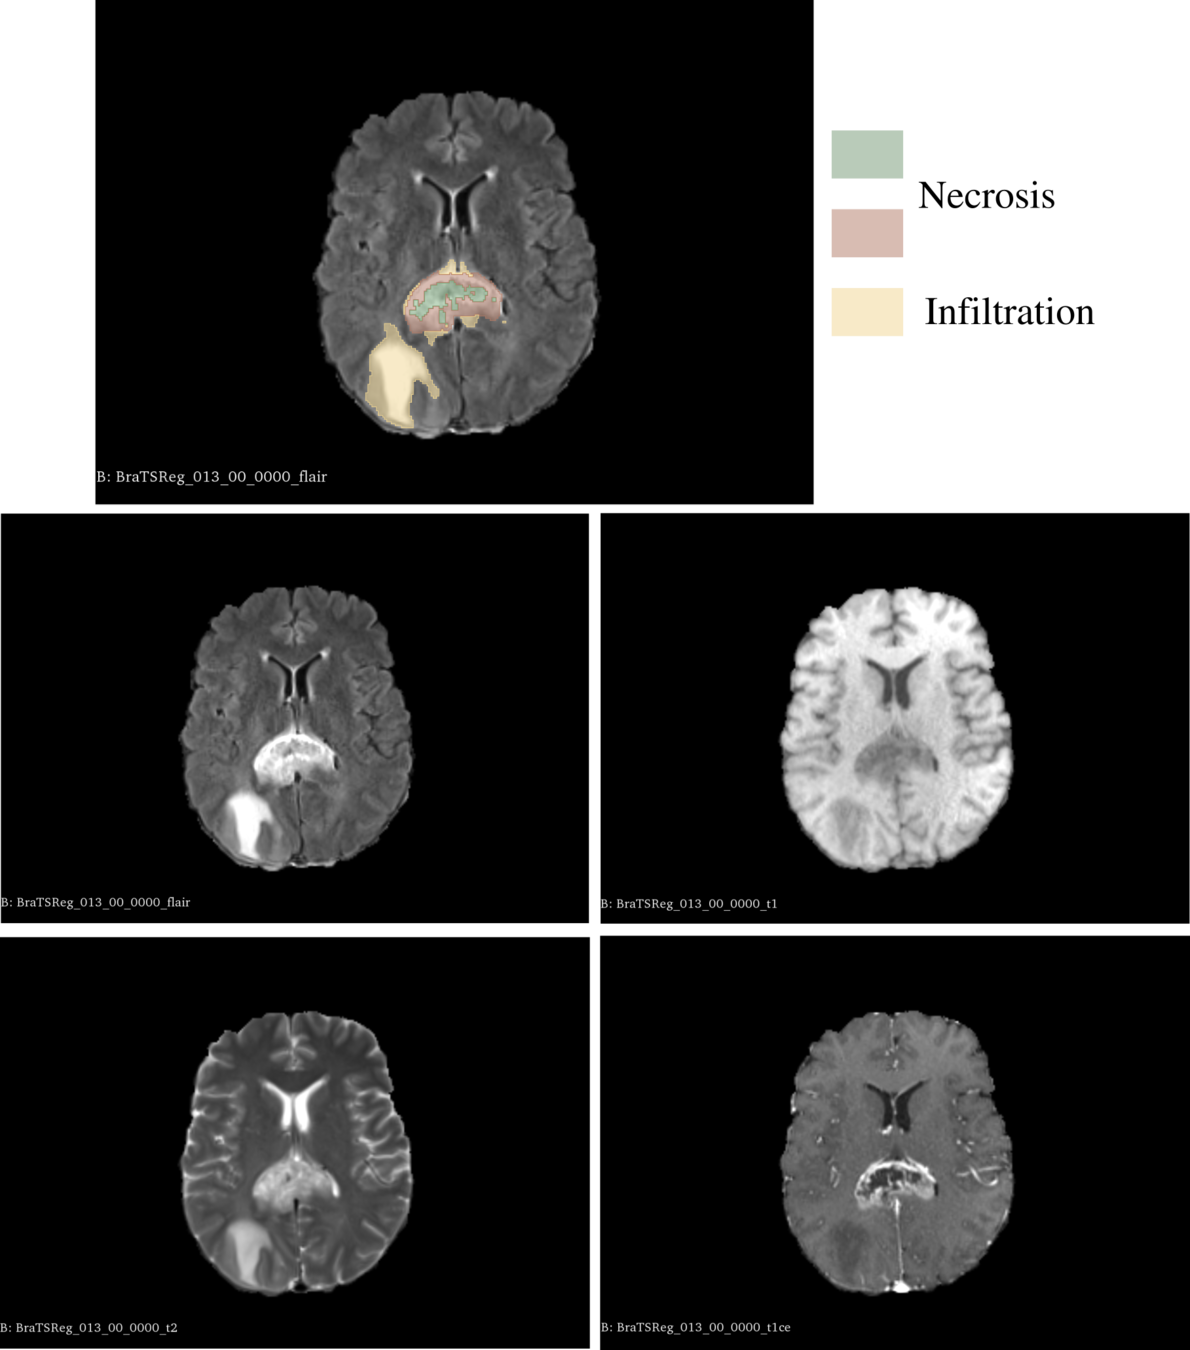

- Necrosis : topological difference

- Mass effect : morphological difference

- Oedema : appearance difference

1. We set \(M_1\) as the topological difference segmentation.